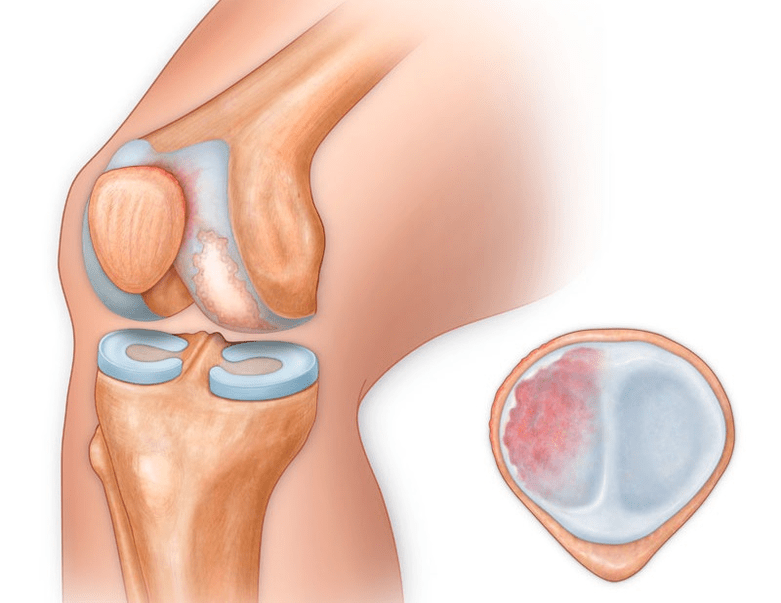

In addition to the inner or outer part of the knee, arthrosis can also affect the surfaces between the patella and the intercondylar groove of the femur.This option is calledpatellofemoral arthrosis.

Its cause is usually a subluxation, fracture or lateralization of the patella.

- injuries (fractures, tears of the meniscus and anterior cruciate ligaments).Unfortunately, in any person, regardless of age, these injuries lead to excessive stress on the cartilage.A fracture of any part of the bone covered with cartilage is accompanied by the formation of an unevenness - a "step".In this area, when it moves, erosion occurs and arthrosis is formed;

- rheumatoid arthritis, Koenig's disease (osteochondritis dissecans), the consequences of purulent inflammation in the joints (gonitis), etc.;